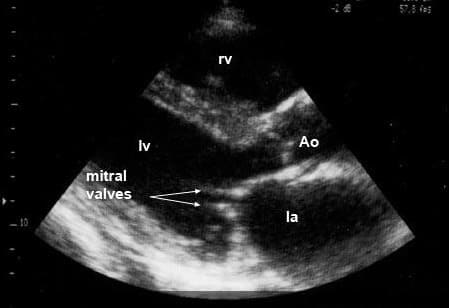

- эхокардиография (УЗИ сердца) проводится с целью визуализации внутренних образований сердца, выявляет изменение толщины и подвижности створок клапана, сужение его отверстия, позволяет измерить площадь сужения. Также при ЭХО – КГ врач определяет степень выраженности нарушений гемодинамики (повышенное давление в левом предсердии, гипертрофию и дилатацию (расширение) левого предсердия и правого желудочка), оценивает степень нарушений кровотока из левого желудочка в аорту (фракция выброса, ударный объем).

На изображении, полученном при эхокардиографии, видны утолщенные створки митрального клапана (mitral valves)